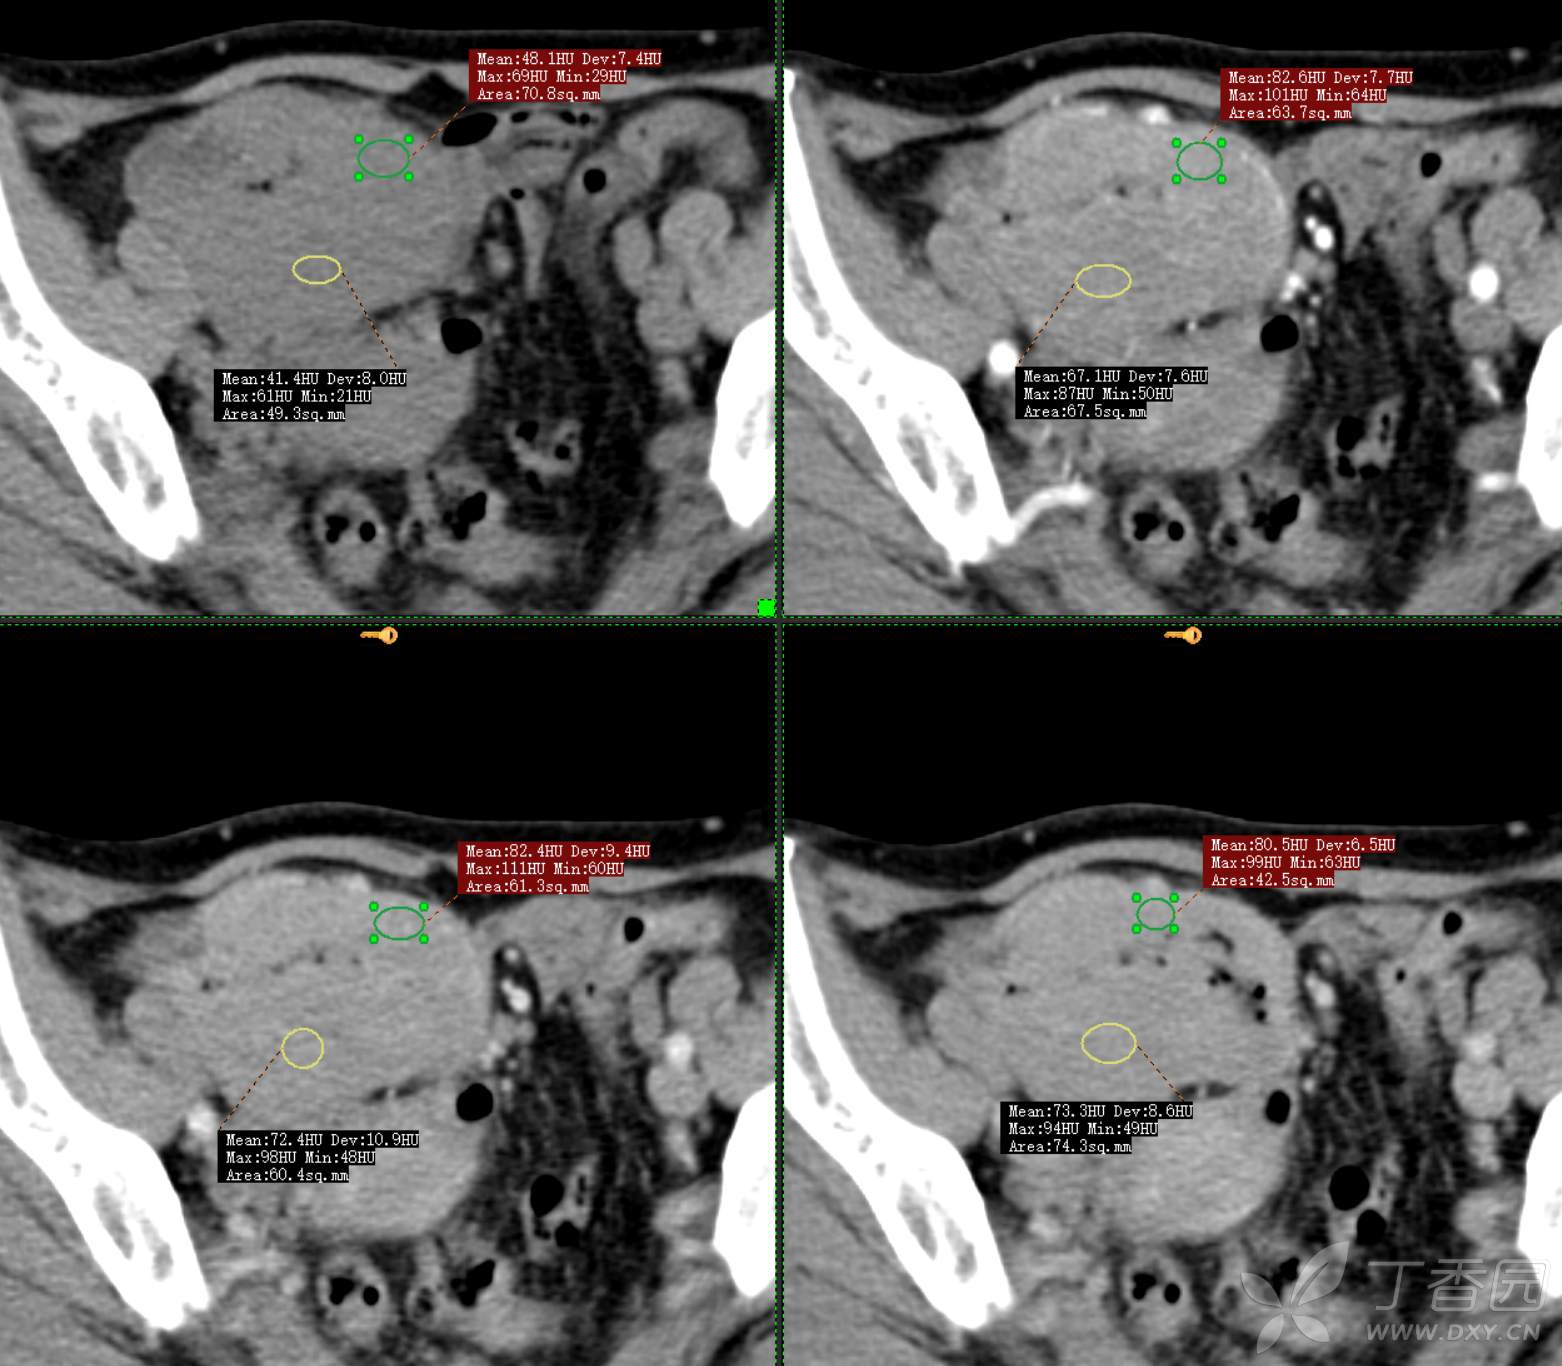

腹组13:患者,女,62岁,大便习惯改变2月余

主 诉: 【大便性状改变2月余】

现病史: 患者2月余前无明显诱因下出现大便次数增多,无明显血便黑便及粘液脓血便,大便次数由1次/日增加至2-3次/日,大便形状变细如小指,偶稀软不成形,无腹痛腹胀腹泻,无恶心呕吐、胸闷气促,肛门排气通畅,无发热盗汗。至当地医院就诊,行肠镜检查发现"回盲部占位"。为进一步治疗,我院门诊拟"回盲部肿瘤"收住入院。